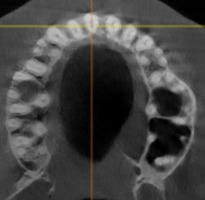

При анализе и описании компьютерной конусно-лучевой томографии (рис. 2а-г) была выявлена генерализованная первичная дегисценция вестибулярной пластинки кости от 1/2 до 3/4 длины корней зубов, зубной ряд целостный, все зубы витальны, кариозных поражений нет. Тип кости 1-2 (Lechkolm и Zarb, 1983), первичная дегисценция вестибулярной костной пластинки превышает пределы возрастной атрофии.

10. Анализ компьютерного томографического обследования

Через 12 месяцев (рис. 7а-г) на срезах компьютерной томограммы 11-ый и 13-ый зубы находятся в костной ткани, при этом костные пики и перегородки укрепились, объем их увеличился; вестибулярно заметен объем костной массы, предположительно компактной формации, исходя из электронной плотности участка. Этим объясняется отсутствие рецидива при лечении рецессии десны как в случае применения аутотрансплантата, также и ТМО (dura mater).